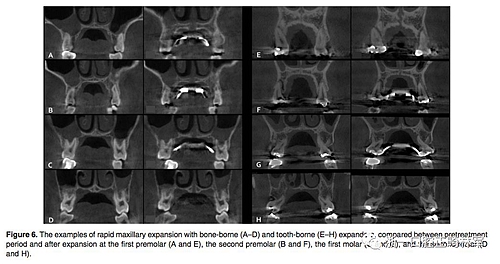

(1)牙支持式和骨支持式快擴(kuò)之間的比較(Figure 6,Table 1)

骨骼變化:腭中縫線在兩組中都以三角形模式被成功打開,鼻底增加最少,硬腭以下5mm平面出被打開最多(P<0.001)。骨骼的擴(kuò)張比牙齒的水平要少。除了第一前磨牙區(qū)域的線性測量值外,骨支持式組顯示擴(kuò)張程度比牙支持式組顯著增加。

牙性變化:兩組的牙槽骨和牙長軸的角度變化都很明顯。牙支持式組在全部區(qū)域都顯示出比骨支持式組更大的頰側(cè)傾斜(P<0.01)。牙支持式組的牙槽骨頰傾更明顯,第二磨牙區(qū)域除外(P <0.05)。在第一前磨牙和第一磨牙,兩組在根尖處的橫向距離增加是相似的。然而,在第二前磨牙和第二磨牙中,牙支持式組發(fā)生根尖橫向距離增加較少。在牙冠水平,僅在第二前磨牙處,兩組之間的擴(kuò)張相似。牙支持式組在第一前磨牙和第一磨牙產(chǎn)生更多的牙冠之間橫向距離增加,而骨支持式更多發(fā)生在第二磨牙。在第一前磨牙和第一磨牙的垂直向變化方面,兩組之間沒有區(qū)別。 第二前磨牙區(qū)頰尖頰傾和腭尖掛下在牙支持式組比骨支持式組更明顯(P <0.05)。在第二磨牙區(qū)域,僅在頰尖頰傾方面兩組有統(tǒng)計(jì)學(xué)差異(P <0.05)。除了第一前磨牙在牙支持式組的頰側(cè)骨開裂明顯(P <0.01)之外,兩組間垂直牙槽骨損失量沒有顯著差異。